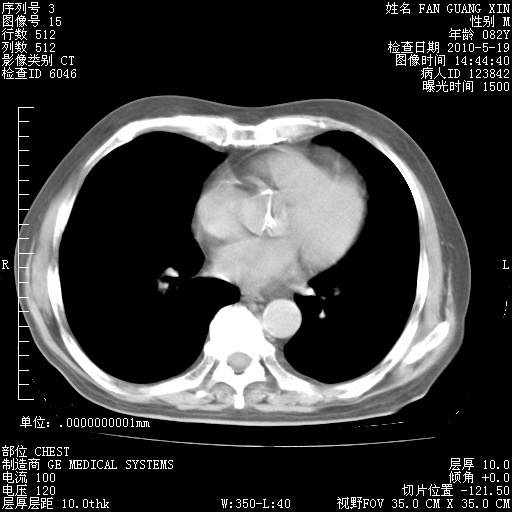

复查肺部CT,明显好转。为什么发热呢?

治疗3周后的肺部CT

治疗3周后的肺部CT纵隔窗